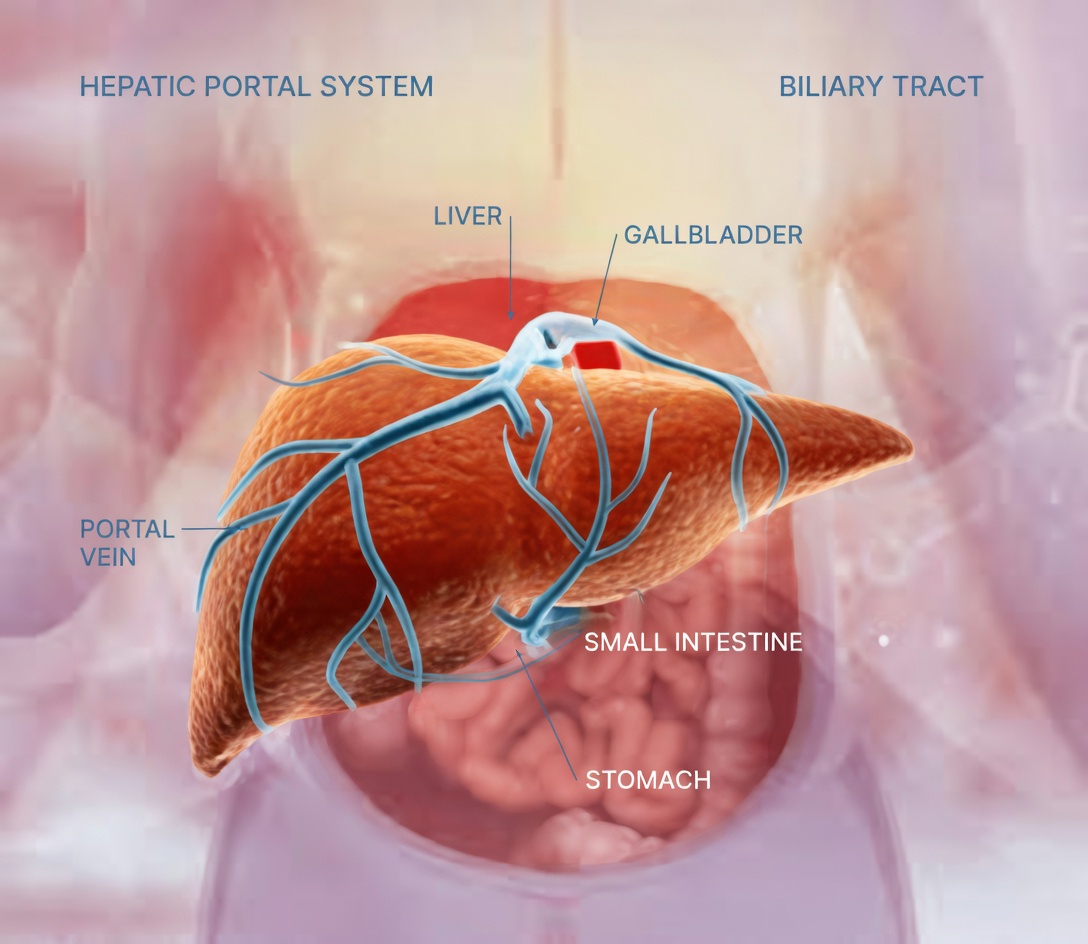

But these small changes may be your body’s way of signaling that your liver is not working as well as it should. Because the liver helps filter toxins, process nutrients, and support digestion, problems can develop quietly at first. Many liver conditions cause little or no pain early on, which is why unusual symptoms often go unnoticed.

8. Swelling or Bloating in the Abdomen

David, 65, dealt with persistent fullness and abdominal swelling that made daily movement uncomfortable.

In more advanced situations, the body may retain fluid in the abdomen, a condition often called ascites. Even before that stage, ongoing swelling or bloating can be an important sign that something is not right.

5. Pale or Clay-Colored Stools

Maria, 54, realized her stools were becoming unusually light in color. The change was subtle but persistent, and it made her uneasy.

Stool that appears pale, gray, or clay-colored can suggest that bile is not flowing normally. Since bile helps give stool its usual brown color, this change may be connected to liver or bile duct problems.